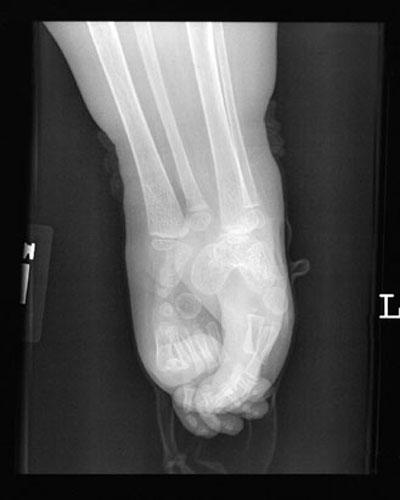

Большинство детей с «сиреномелией» - редким врожденным пороком развития – так называемым «синдромом русалки» погибают в первые часы после появления на свет из-за многочисленных сопутствующих дефектов развития…В настоящее время в мире известны три случая спасения детей с подобным синдромом – это американка Тифани Йоркс, успешно перенесшая операцию по разделению ног 19 лет назад,трехлетняя перуанская девочка Милагрос Серрон, последняя операция по разделению ног которой была проведена летом этого года, и Шилох Пепин, единственная, кого так и не прооперировали…

Кроме сросшихся ног у девочки при рождении не досчитались мочевого пузыря, матки, толстого кишечника, влагалища…У неё была лишь одна недоразвитая почка и один яичник…